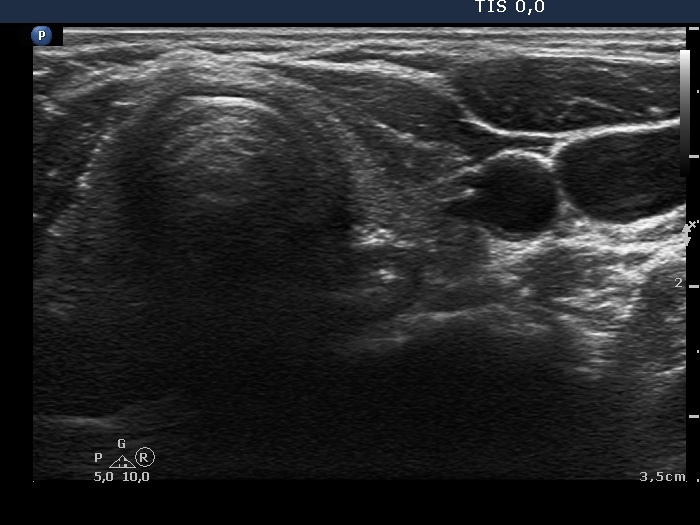

Ultrasonography: The thyroid was moderately hypoechogenic. There were two more hypoechogenic lesions in the dorsal part of the right lobe.

Ultrasonography: The thyroid was unchanged. The lesions in the dorsal part of the right lobe increased in size and a small hypoechogenic area appeared in the ventral part of the left lobe.